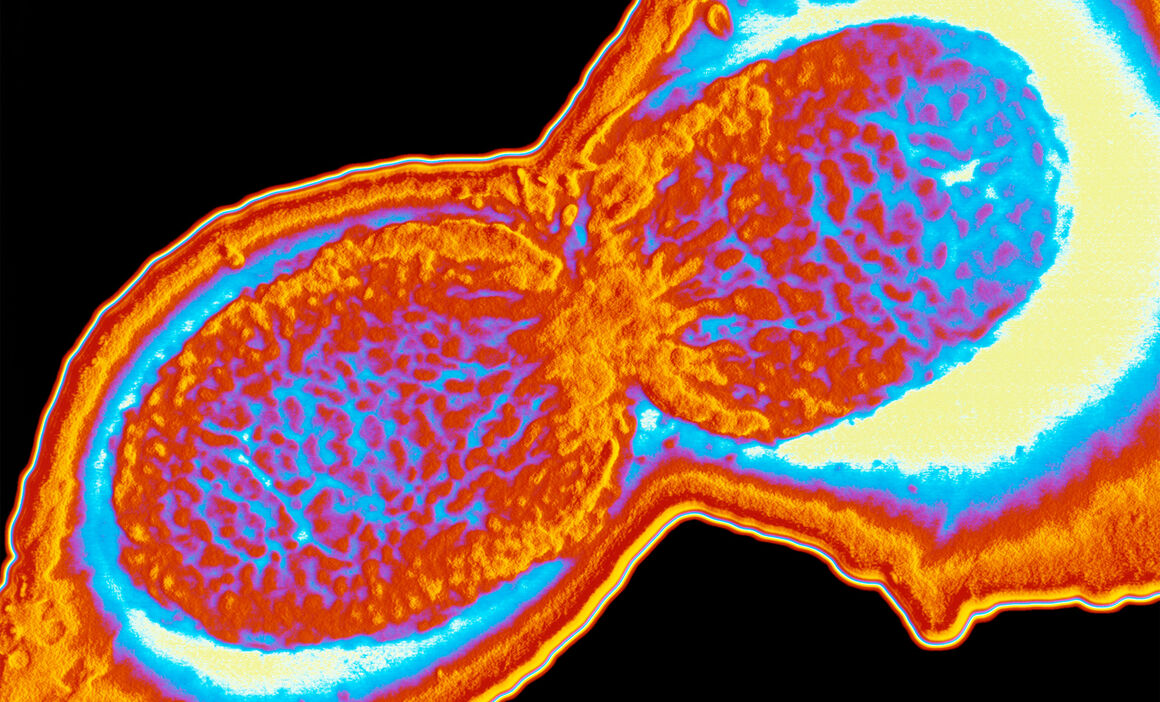

Shigellosis is a gastrointestinal infection caused by Shigella bacteria. It is caught by ingesting material contaminated by human faeces, via direct oral-anal (or person-to-person) contact or hands/objects which have been in contact with faeces. The infective dose is extremely small, 10−100 organisms, making shigellosis easily transmissible. Infection can also result from contaminated food or water. Symptoms include acute diarrhoea, often accompanied by fever, abdominal pain and the presence of blood in stools. Most infections are self-limiting, lasting around 5−7 days, and do not require antimicrobial treatment. Treatment decreases the duration of symptoms by 1−2 days and may reduce the likelihood of onward transmission. Severe infection can also occur, especially in immunocompromised patients.